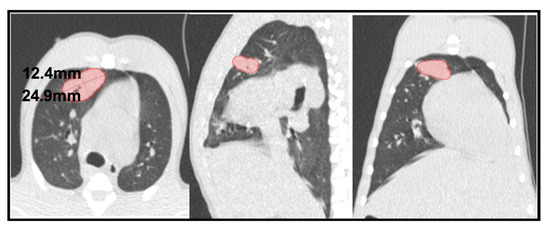

2.4. TB Lung Lesions Analysis from CT Images

- A.

- Micronodule is a small solid lung nodule with smooth margins.

- B.

- Consolidation (also referred to as consolidated lesion) is a pneumonic patch or necrotizing consolidative process that occupies and even destroys alveoli, and it is described in CT images as a soft tissue lesion within lung parenchyma showing irregular margins.

- C.

- D.

- Pleural distance is defined as the distance between the margin of each consolidation to the closest pleura or fissure.